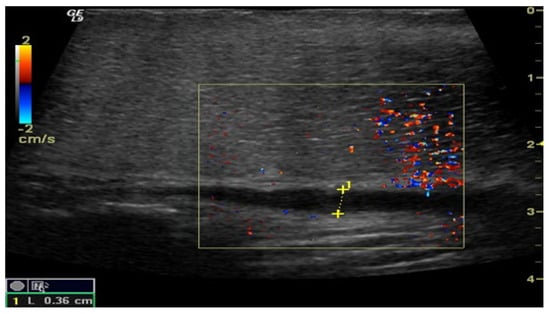

Figure 3.

Penile CDUS during pharmacologically induced erection. Signs of veno-occlusive ED: diameter of the deep dorsal vein is enlarged, indicating venous insufficiency.